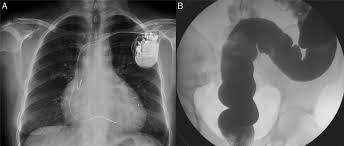

ANSM 10 de abril de 2020   se han notificado 100 casos de reacciones adversas en relación con medicamentos utilizados en pacientes infectados con COVID-19, incluidos 82 casos graves, con 4 casos de muerte. La mayoría de las reacciones adversas notificadas se dividen a partes iguales entre lopinavir-ritonavir e hidroxicloroquina. De los 53 casos notificados de efectos adversos cardíacos, 43 fueron por hidroxicloroquina, sola o combinada con azitromicina; 7 de ellos con muerte súbita, de los que 3 fueron reanimados con desfribilador; 12 fueron transtornos del ritmo cardíaco (en ECG o síntomas compatibles como síncope) y de la conducción (alargamiento del intervalo QT del ECG).